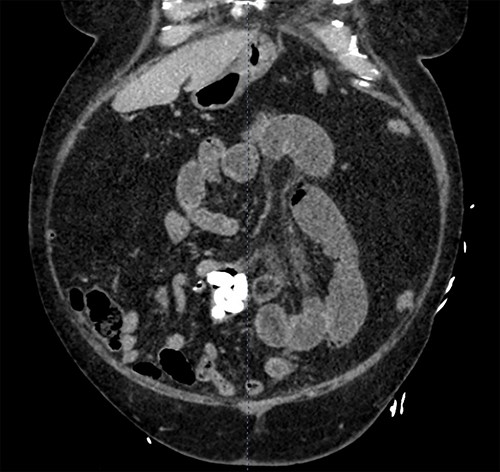

In the Emergency Department, his temperature was 97.2 F, HR87reg, BP 186/94, RR18, and his SpO2 98% on room air. His abdomen was diffusely tender, distended and tympanic. His WBC was 11.5, Alk Phos 67, Tbili 2.2. A CT scan of the abdomen and pelvis with contrast was obtained (Fig. 1) revealing a dilatation of the distal jejunum with air fluid levels and fecalization. Seven, oval-shaped calculi measuring approximately 1.3 cm each were distal to the area of fecalization. Immediately distal to the most distal calculus, a circumferential suture line consistent with previous small bowel anastomosis was identified. Post cholecystectomy status was verified; bile ducts were not dilated and there was no pneumobilia.

A CT scan of the abdomen and pelvis with contrast revealing a dilatation of the distal jejunum with air fluid levels and fecalization.